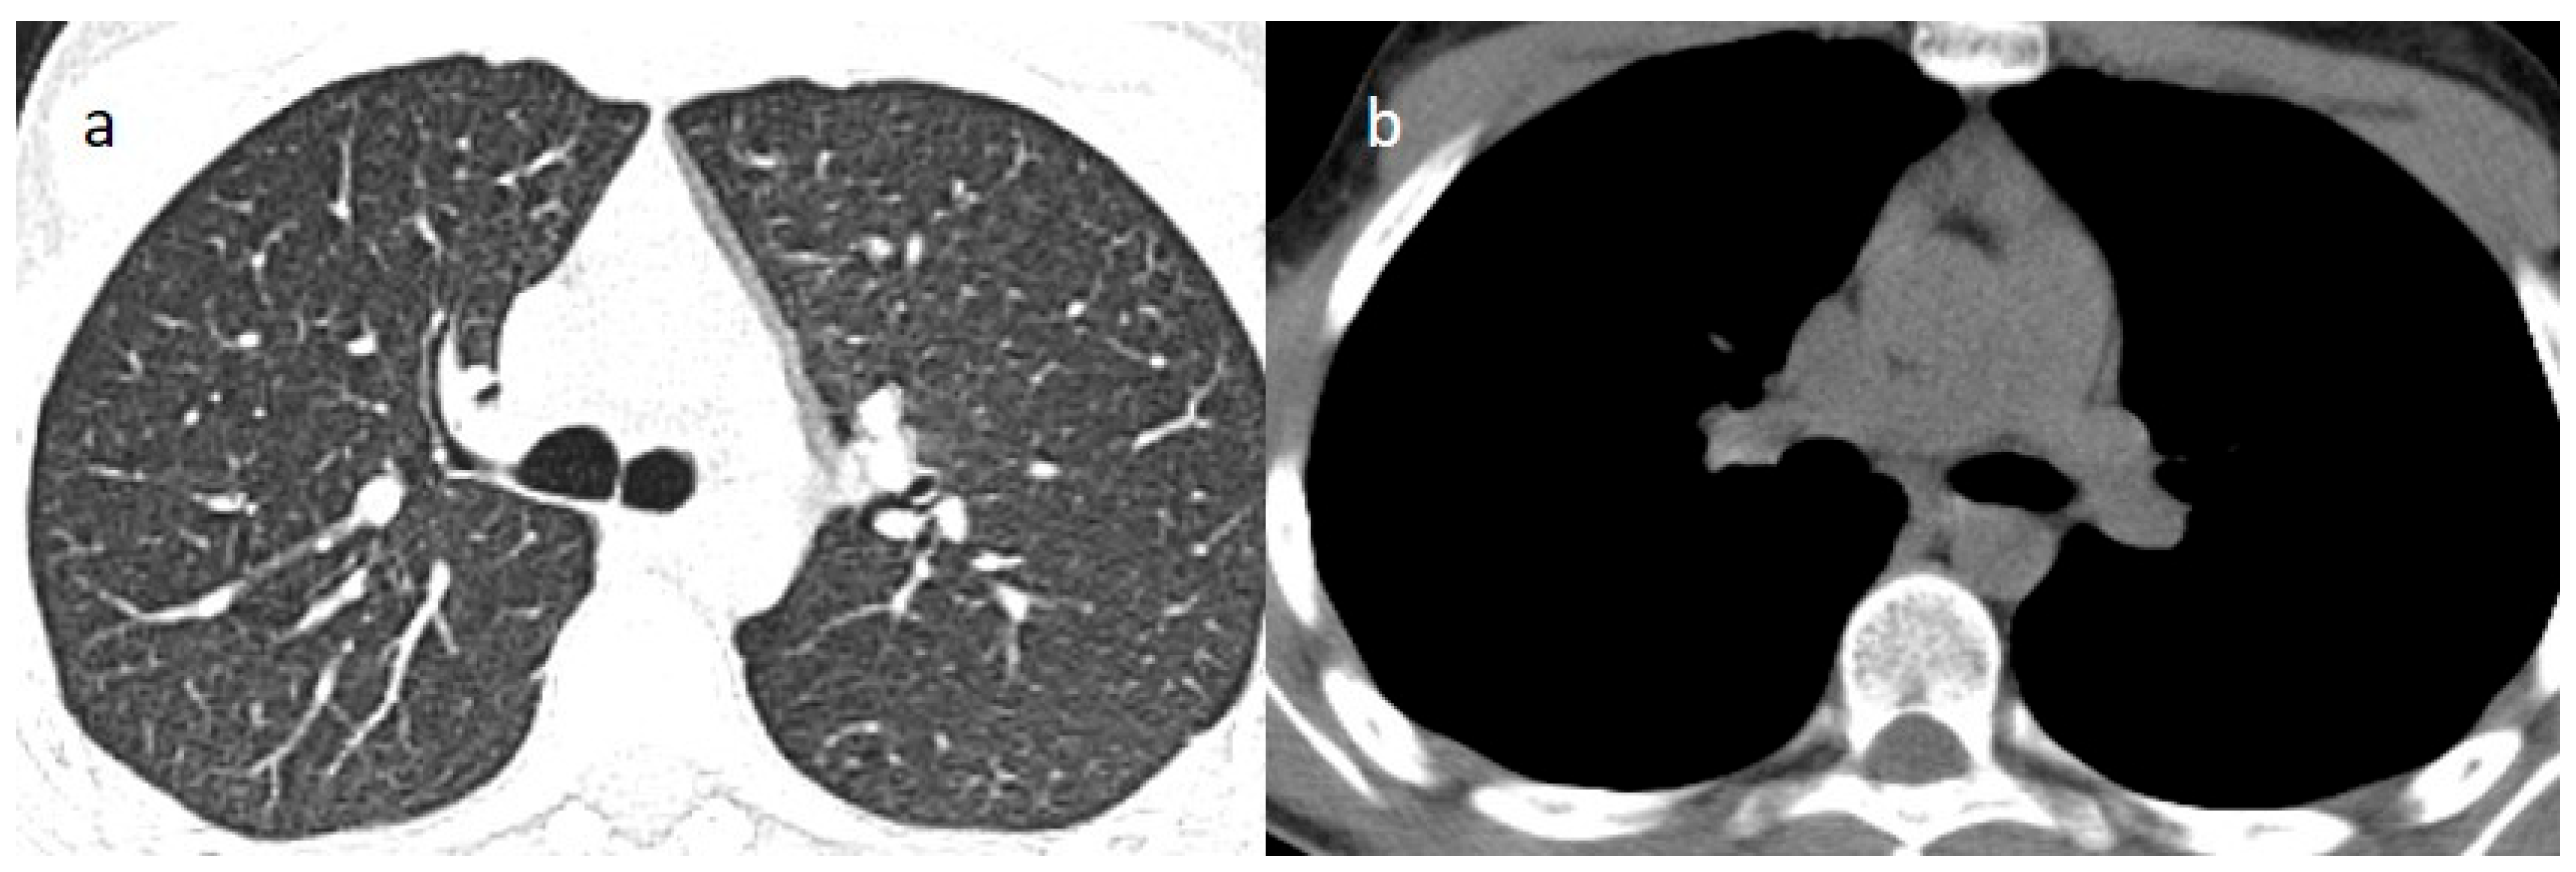

2. Case Presentations

3.2. Thymic Hyperplasia in COVID-19 Infection and Vaccination and the Role of Multimodality Imaging